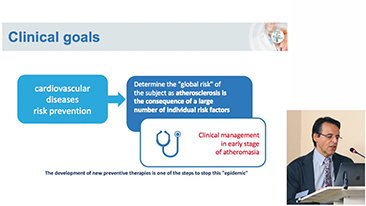

Covid-19: un momento critico per persone e dispositivi

A causa del Coronavirus, gli ospedali e il personale medico hanno sviluppato nuove pratiche di lavoro che comportano, nei contesti di assistenza acuta, il distanziamento sociale, l'uso rigoroso di dispositivi di protezione individuale (DPI), il lavaggio delle mani e la disinfezione quotidiana delle attrezzature. Le apparecchiature portatili, altamente mobili e versatili sono diventate sempre pi├╣ richieste nei punti di cura (POC), in particolare quando i reparti e le sale operatorie sono distribuiti su pi├╣ piani e lŌĆÖutilizzo di dispositivi specialistici ├© importante.